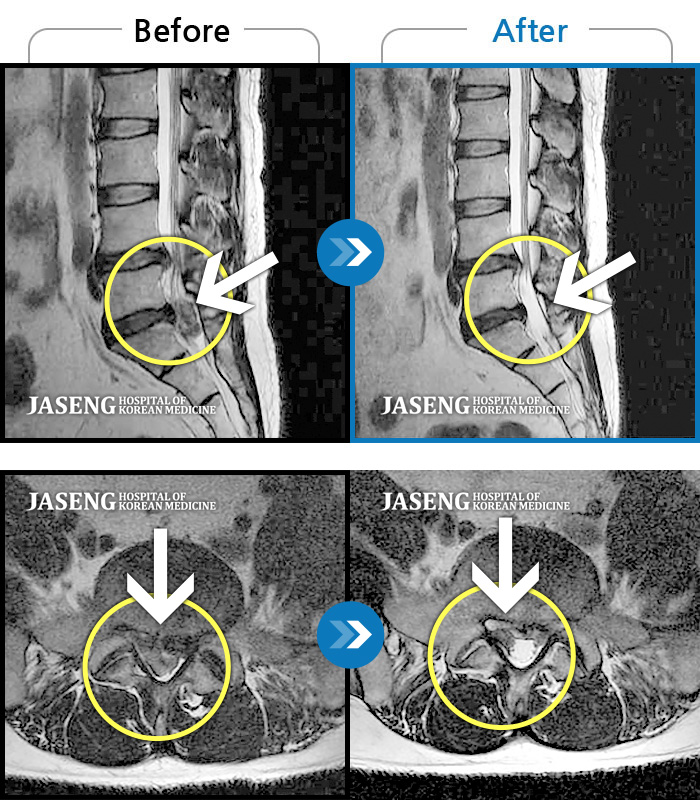

허리디스크

잠실 · 한상욱 원장

허리, 우측 엉치와 다리 후면 및 발끝까지 저림과 통증이 심하고 힘까지 빠진다.

촬영시기

2022.06.15 ~ 2022.11.11

2022.12.02